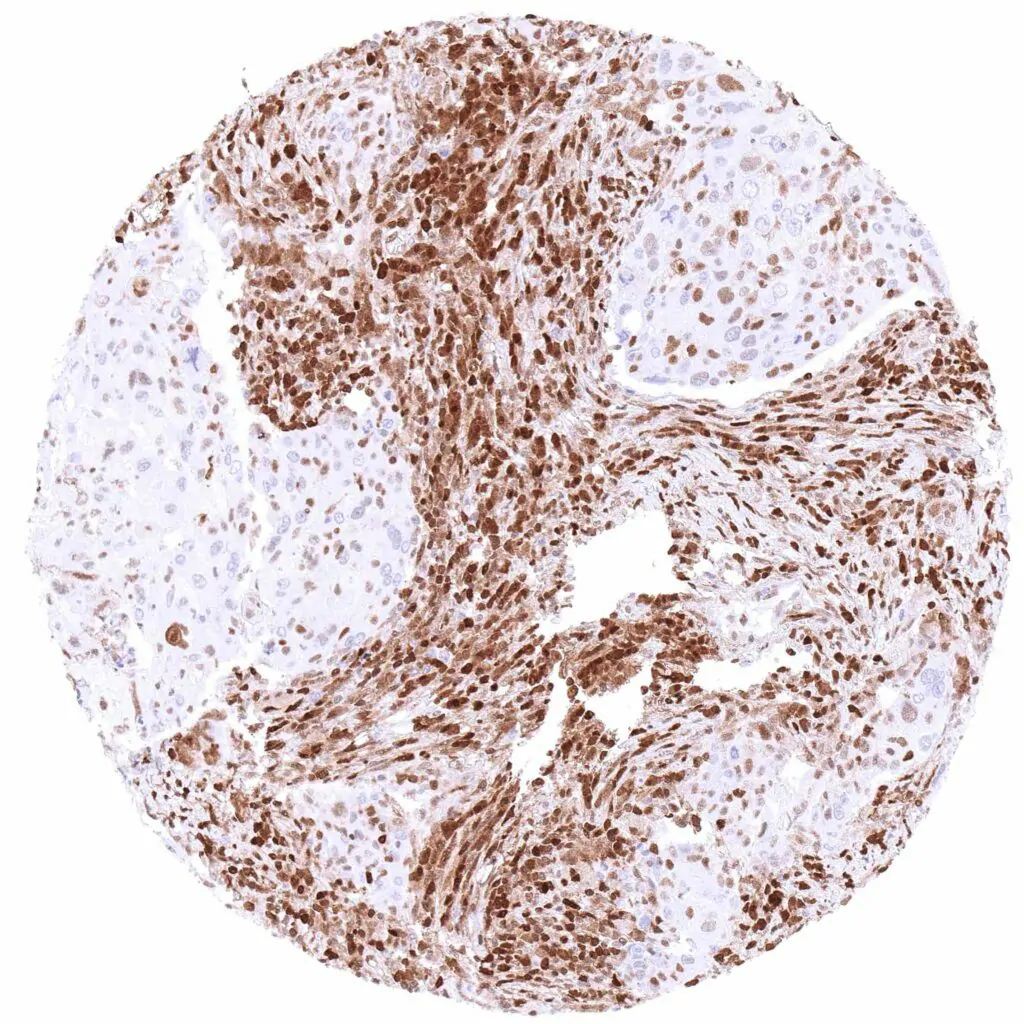

p27 Kip1 antibody [HMV3970] HistoMAX™

Soft tissue – Leiomyosarcoma with weak, predominantly nuclear p27 staining of few cells.